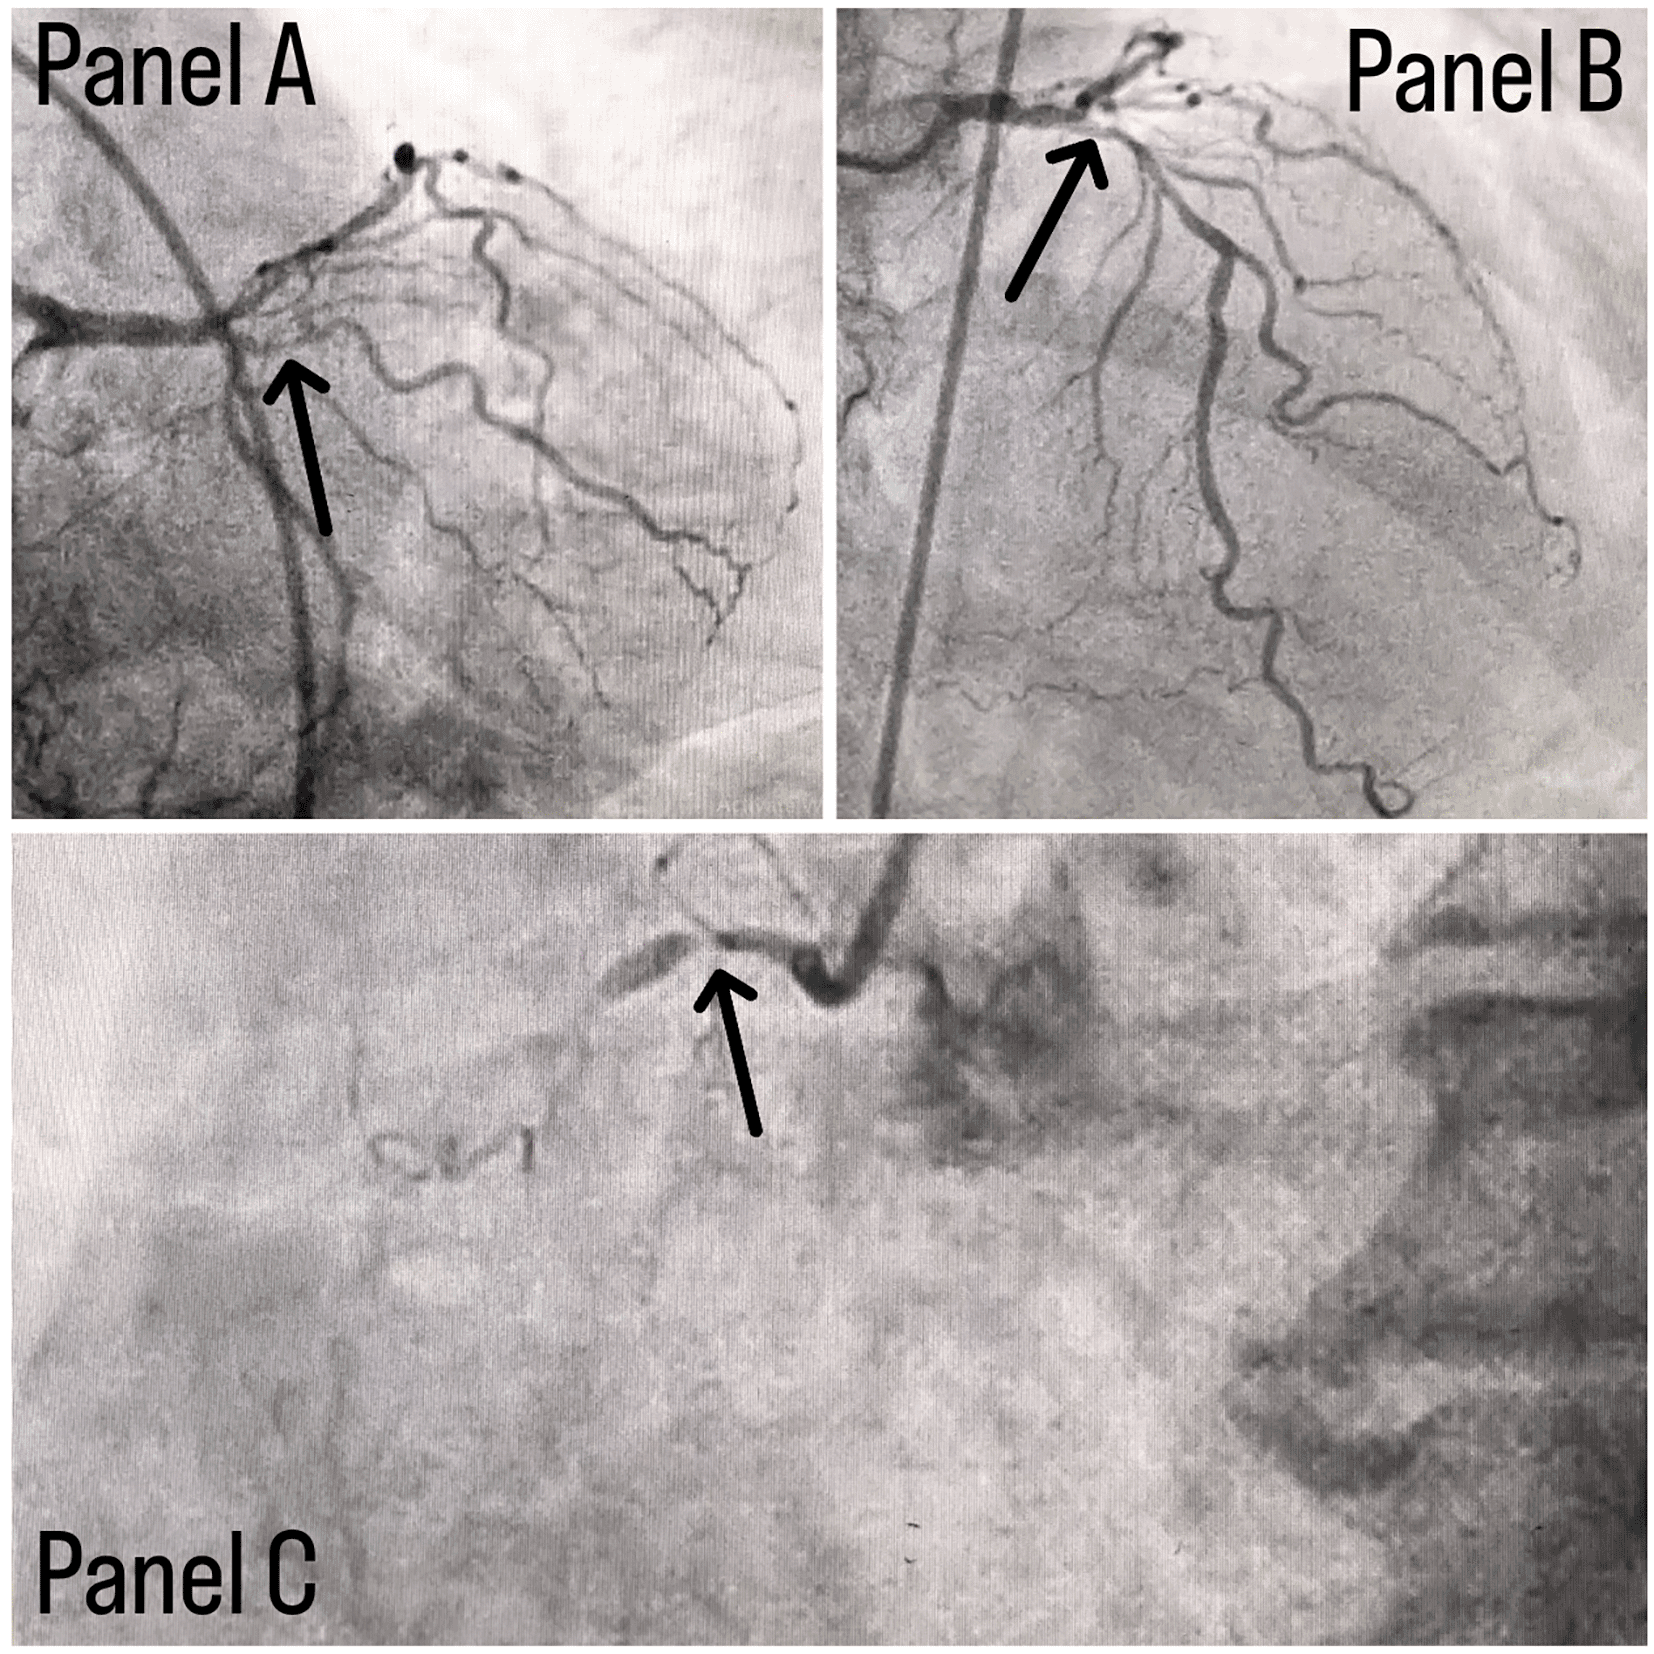

Coronary angiography was done and a triple vessel coronary artery disease was diagnosed as shown in Figure 1; in which, panel A shows stenosis in proximal Left circumflex artery (LCX) with a black arrow, panel B shows a stenotic lesion in proximal Left anterior descending artery (LAD) with a black arrow and panel C shows 100% stenosed Right coronary artery (RCA) with a black arrow. A subclavian puncture was taken to look for a subclavian artery considering the claudication symptoms of the patient and peripheral vascular disease was diagnosed with bilateral subclavian artery stenosis as shown in Figure 2, in which panel A shows right subclavian artery stenosis and panel B shows left subclavian artery stenosis marked with yellow arrows. Considering the severity of claudication pain in our case, bilateral renal and femoral arteries were also checked via aortic flush and bilateral renal artery ostial stenosis was seen. Figure 3 panel A shows right renal ostial stenosis and panel B shows left renal ostial stenosis marked with red arrows.